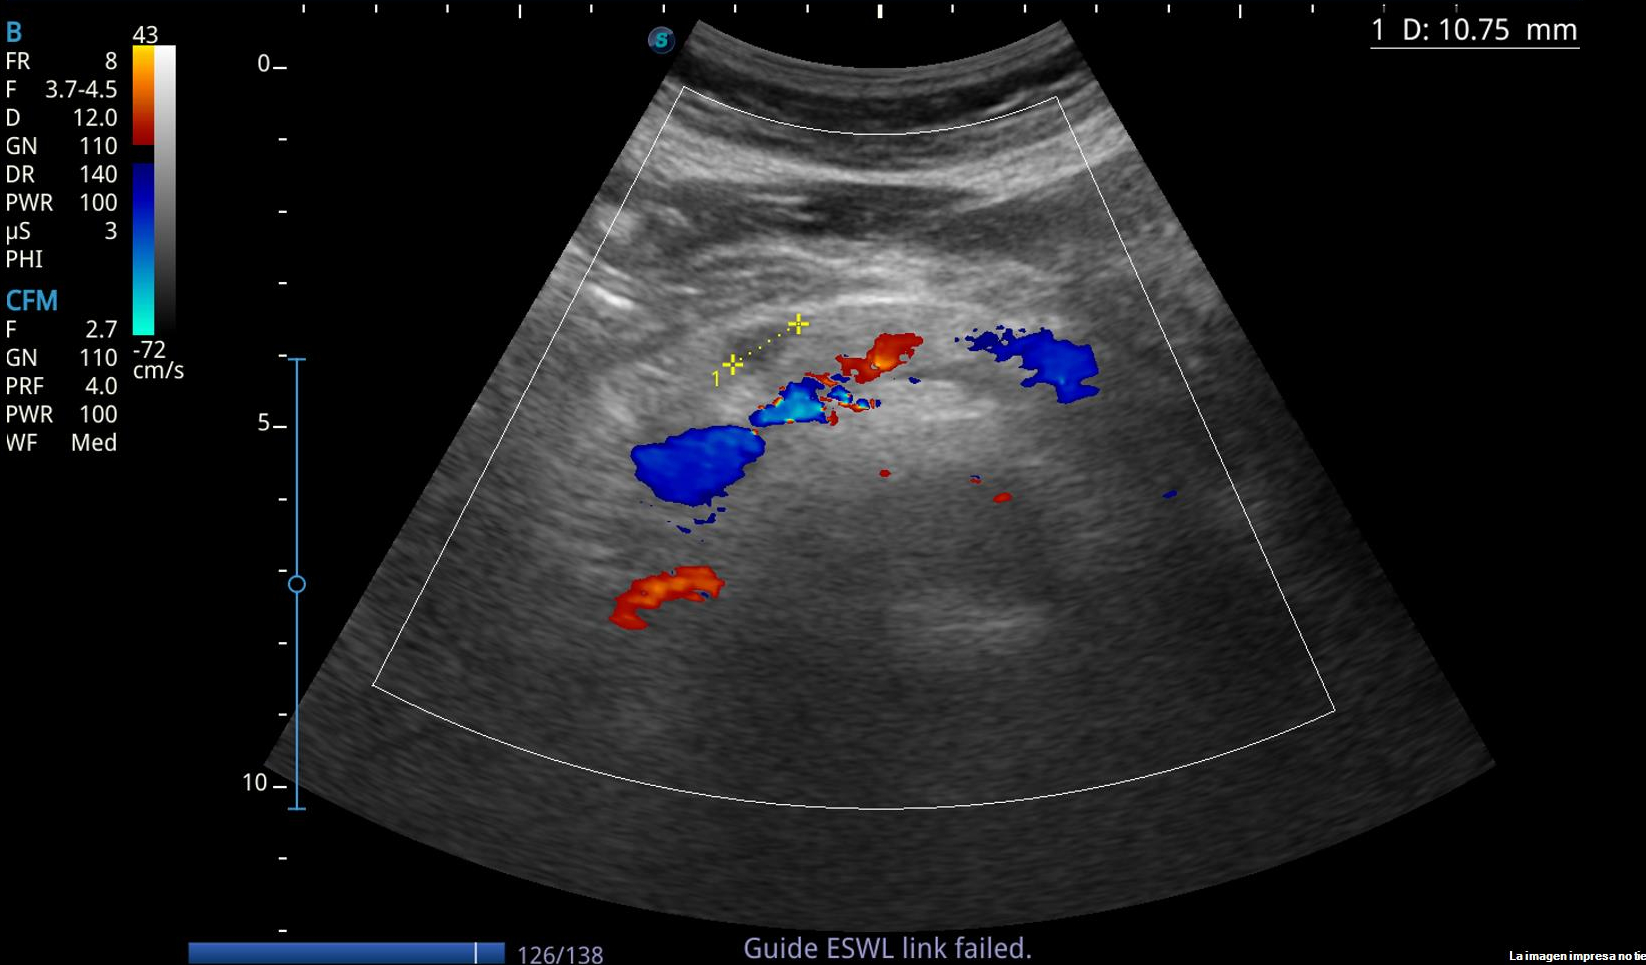

Hallazgos ecográficos

Lesión anecoica bien circunscrita de paredes lisas, con refuerzo posterior, de 1 cm de longitud, localizada en cuerpo pancreático, sin captación Doppler.

Pseudoquiste: imagen anecoica/hipoecoica, borde lisos con o sin tabicaciones/detritus en su interior, 70% en cuerpo pancreático. No captación Doppler.

Cistoadenoma seroso: Sin captación Doppler

Cistoadenoma mucinoso: heterogénea, septos irregulares, con calcificaciones, cuerpo y cola pancreático. Captación Doppler.

Carcinoma papilar intraductal: heteroecoico, bordes irregulares, calcificaciones, conducto Wirsung dilatado, mayor de 2 mm. Captación Doppler.